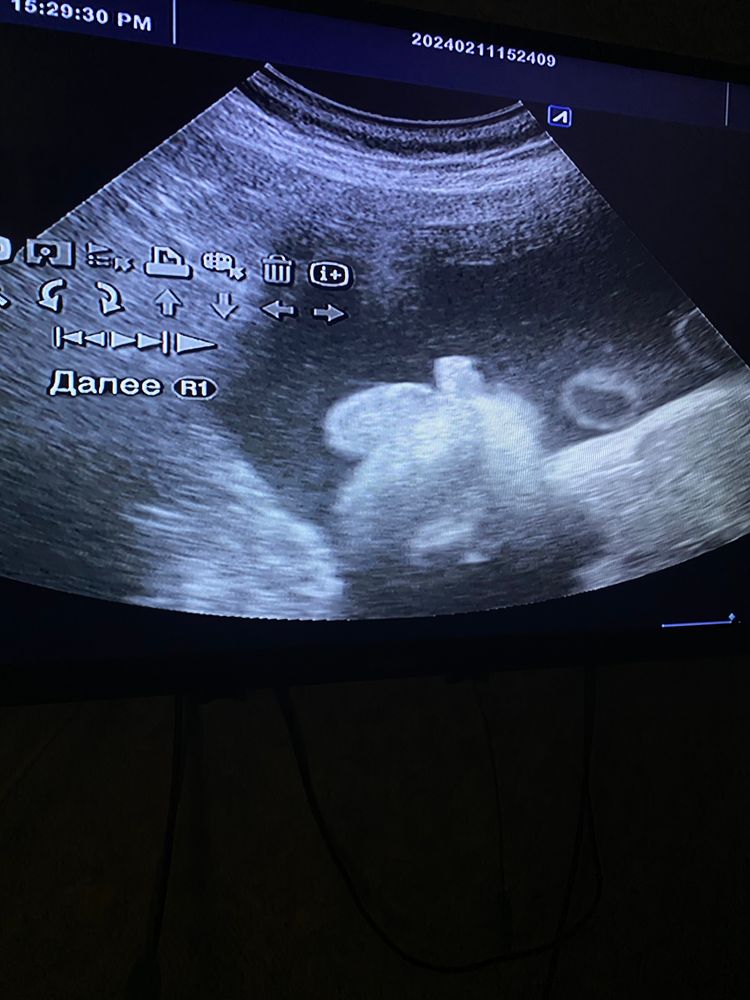

прилагаю фото червячка с последнего узи

А то что вверх торчит, то точно оно? Просто я вижу попку и ноги вниз. а то что сверху я хз ,что это. Но я б пошла ещё куда нибудь😁. Это ж какие нервы перед родами

Таня, вот сама не очень понимаю,врач сказал что точно мужик,я уже два дня на нервах,завтра попытаюсь в жк напроситься на узи

Мальчик, тут ни с чем не спутать.